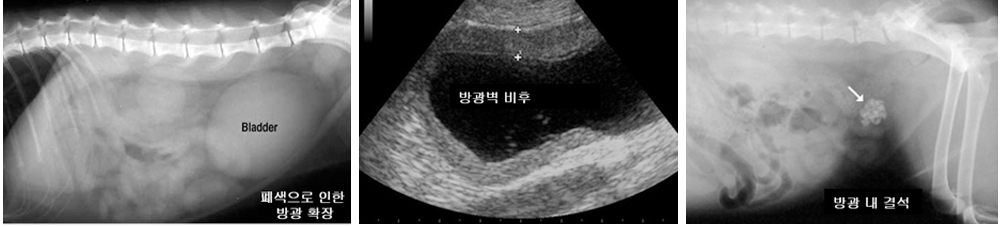

3. 방사선 검사 및 초음파 검사 상 확장된 방광 확인

1. 방사선 검사 및 초음파 검사를 통한 비뇨기 내 결석 확인

2. 방광 초음파 검사 결과 방광염 소견 확인